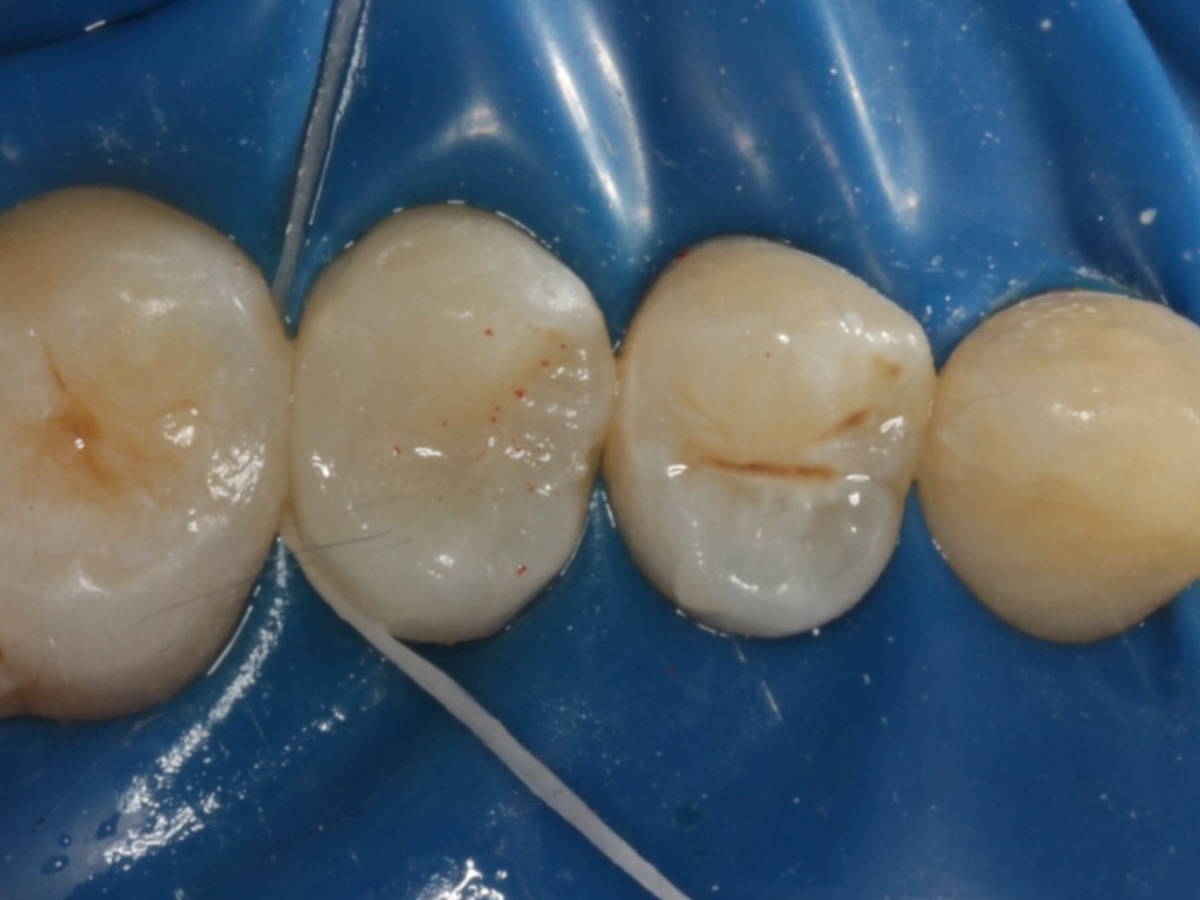

Abbildung 19

Röntgenkontrolle: approximal fast auf Knochenniveau endender spaltfreier Füllungsrand dank interproximaler tieferer Verlängerung der Evolve Matrize